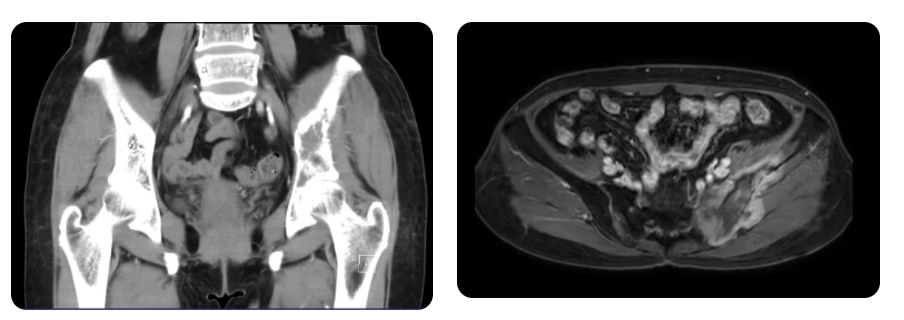

近日,贵州医科大学附属医院骨科骨肿瘤团队成功完成全省首例半骨盆 + 半骶骨切除联合 3D 打印肿瘤假体置换手术,实现了贵州骨肿瘤外科手术在累及骨盆、骶骨手术禁区的突破。患者王女士(化名),因左髋部进行性疼痛不适 4 月余且体重消瘦 3公斤,前往当地医院就诊。在当地医院经初查,考虑为左侧骨盆肿瘤,后辗转多家医院,最终于今年 7 月转至我院骨肿瘤中心。经穿刺病理检查,确诊为“骨盆恶性肿瘤骨肉瘤”。

骨肉瘤是骨骼系统最常见的原发性恶性肿瘤,其恶性程度极高,尤其在青少年中更为常见。成年人骨盆区域的骨肉瘤发病率相对较低,但由于其血行转移发生早、发生率高,病情进展迅速,治疗难度极大,因手术切除困难导致临床预后较差。王女士病情复杂,肿瘤范围广泛,累及左侧骨盆及左侧骶骨,因骨盆骶骨区域解剖结构复杂,涉及泌尿系统、消化系统、大血管、大神经等,手术难度极大。